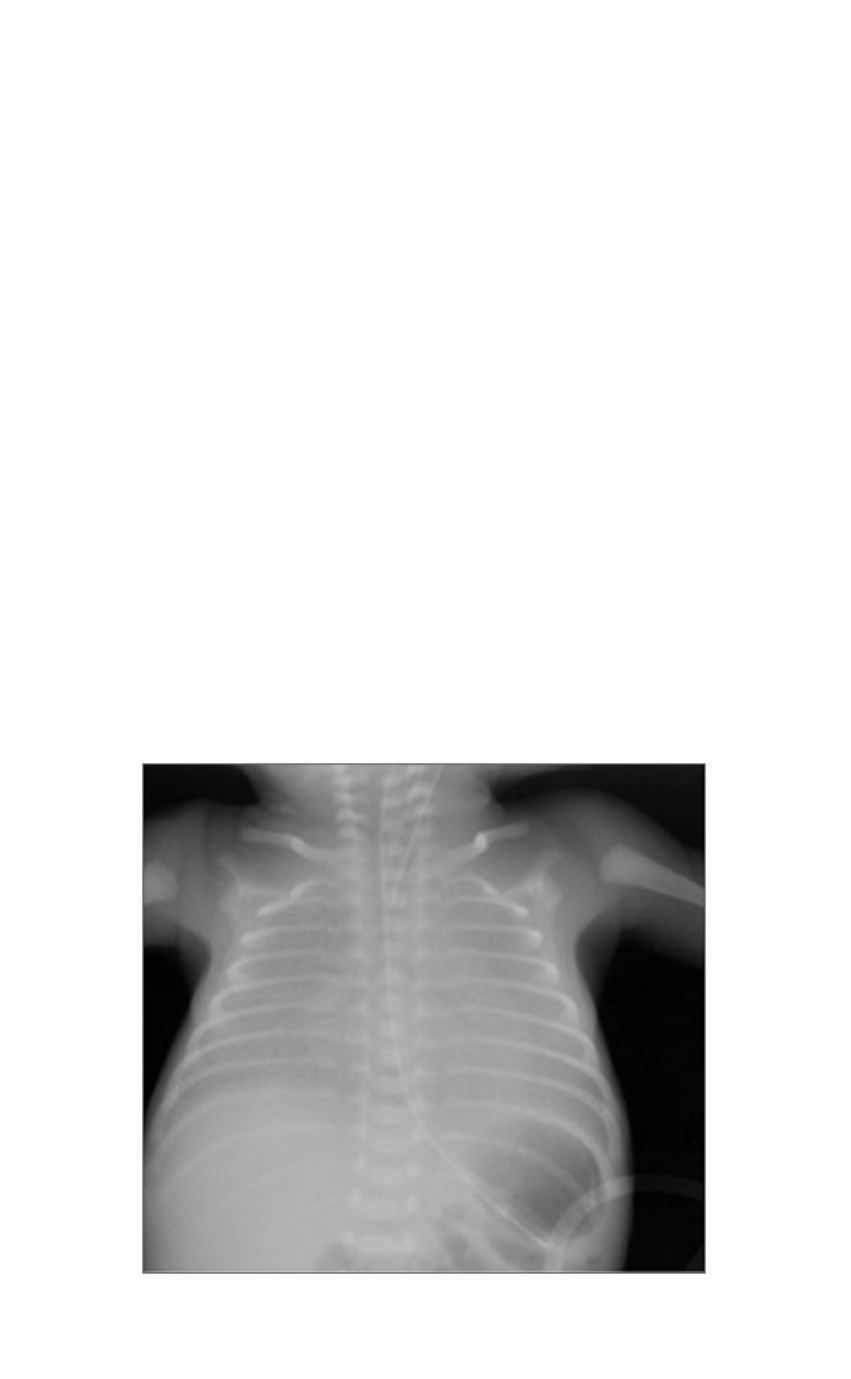

Na admissão, apresentava-se com desconforto respiratório grave e radiografia de tórax (Figura 1) evidenciava hipotransparência difusa bilateral. No exame físico, entrada de ar diminuída bilateralmente. Frequência respiratória de 78 irpm, retrações subcostais e de fúrcula esternal presentes. Frequência cardíaca de 158 bpm e ausculta cardíaca normal. Restante do exame físico sem alterações.

Figura 1. Radiografia simples de tórax na admissão na UTI Neonatal.